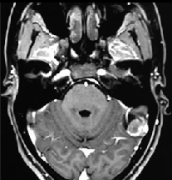

弥漫性脑干胶质瘤 (DIPG)是一种以儿童常见的异质性 脑胶质瘤 ,呈双峰的年龄分布,儿童脑干胶质瘤在脑肿瘤高达20%,成人 脑干胶质瘤 仅占脑胶质瘤的1%...

脑干胶质瘤,主要由星形胶质细胞瘤和少突胶质细胞瘤组成,约占成人中全部原发性胶质瘤的2%。那么,脑干胶质瘤怎么引起的?如何治疗...

弥漫性脑干胶质瘤不能完全治愈。弥漫性脑干胶质瘤是儿童和青少年常见的脑干胶质瘤类型。肿瘤的范围通常广泛,通常涉及整个脑干。脑干是人体较重要...